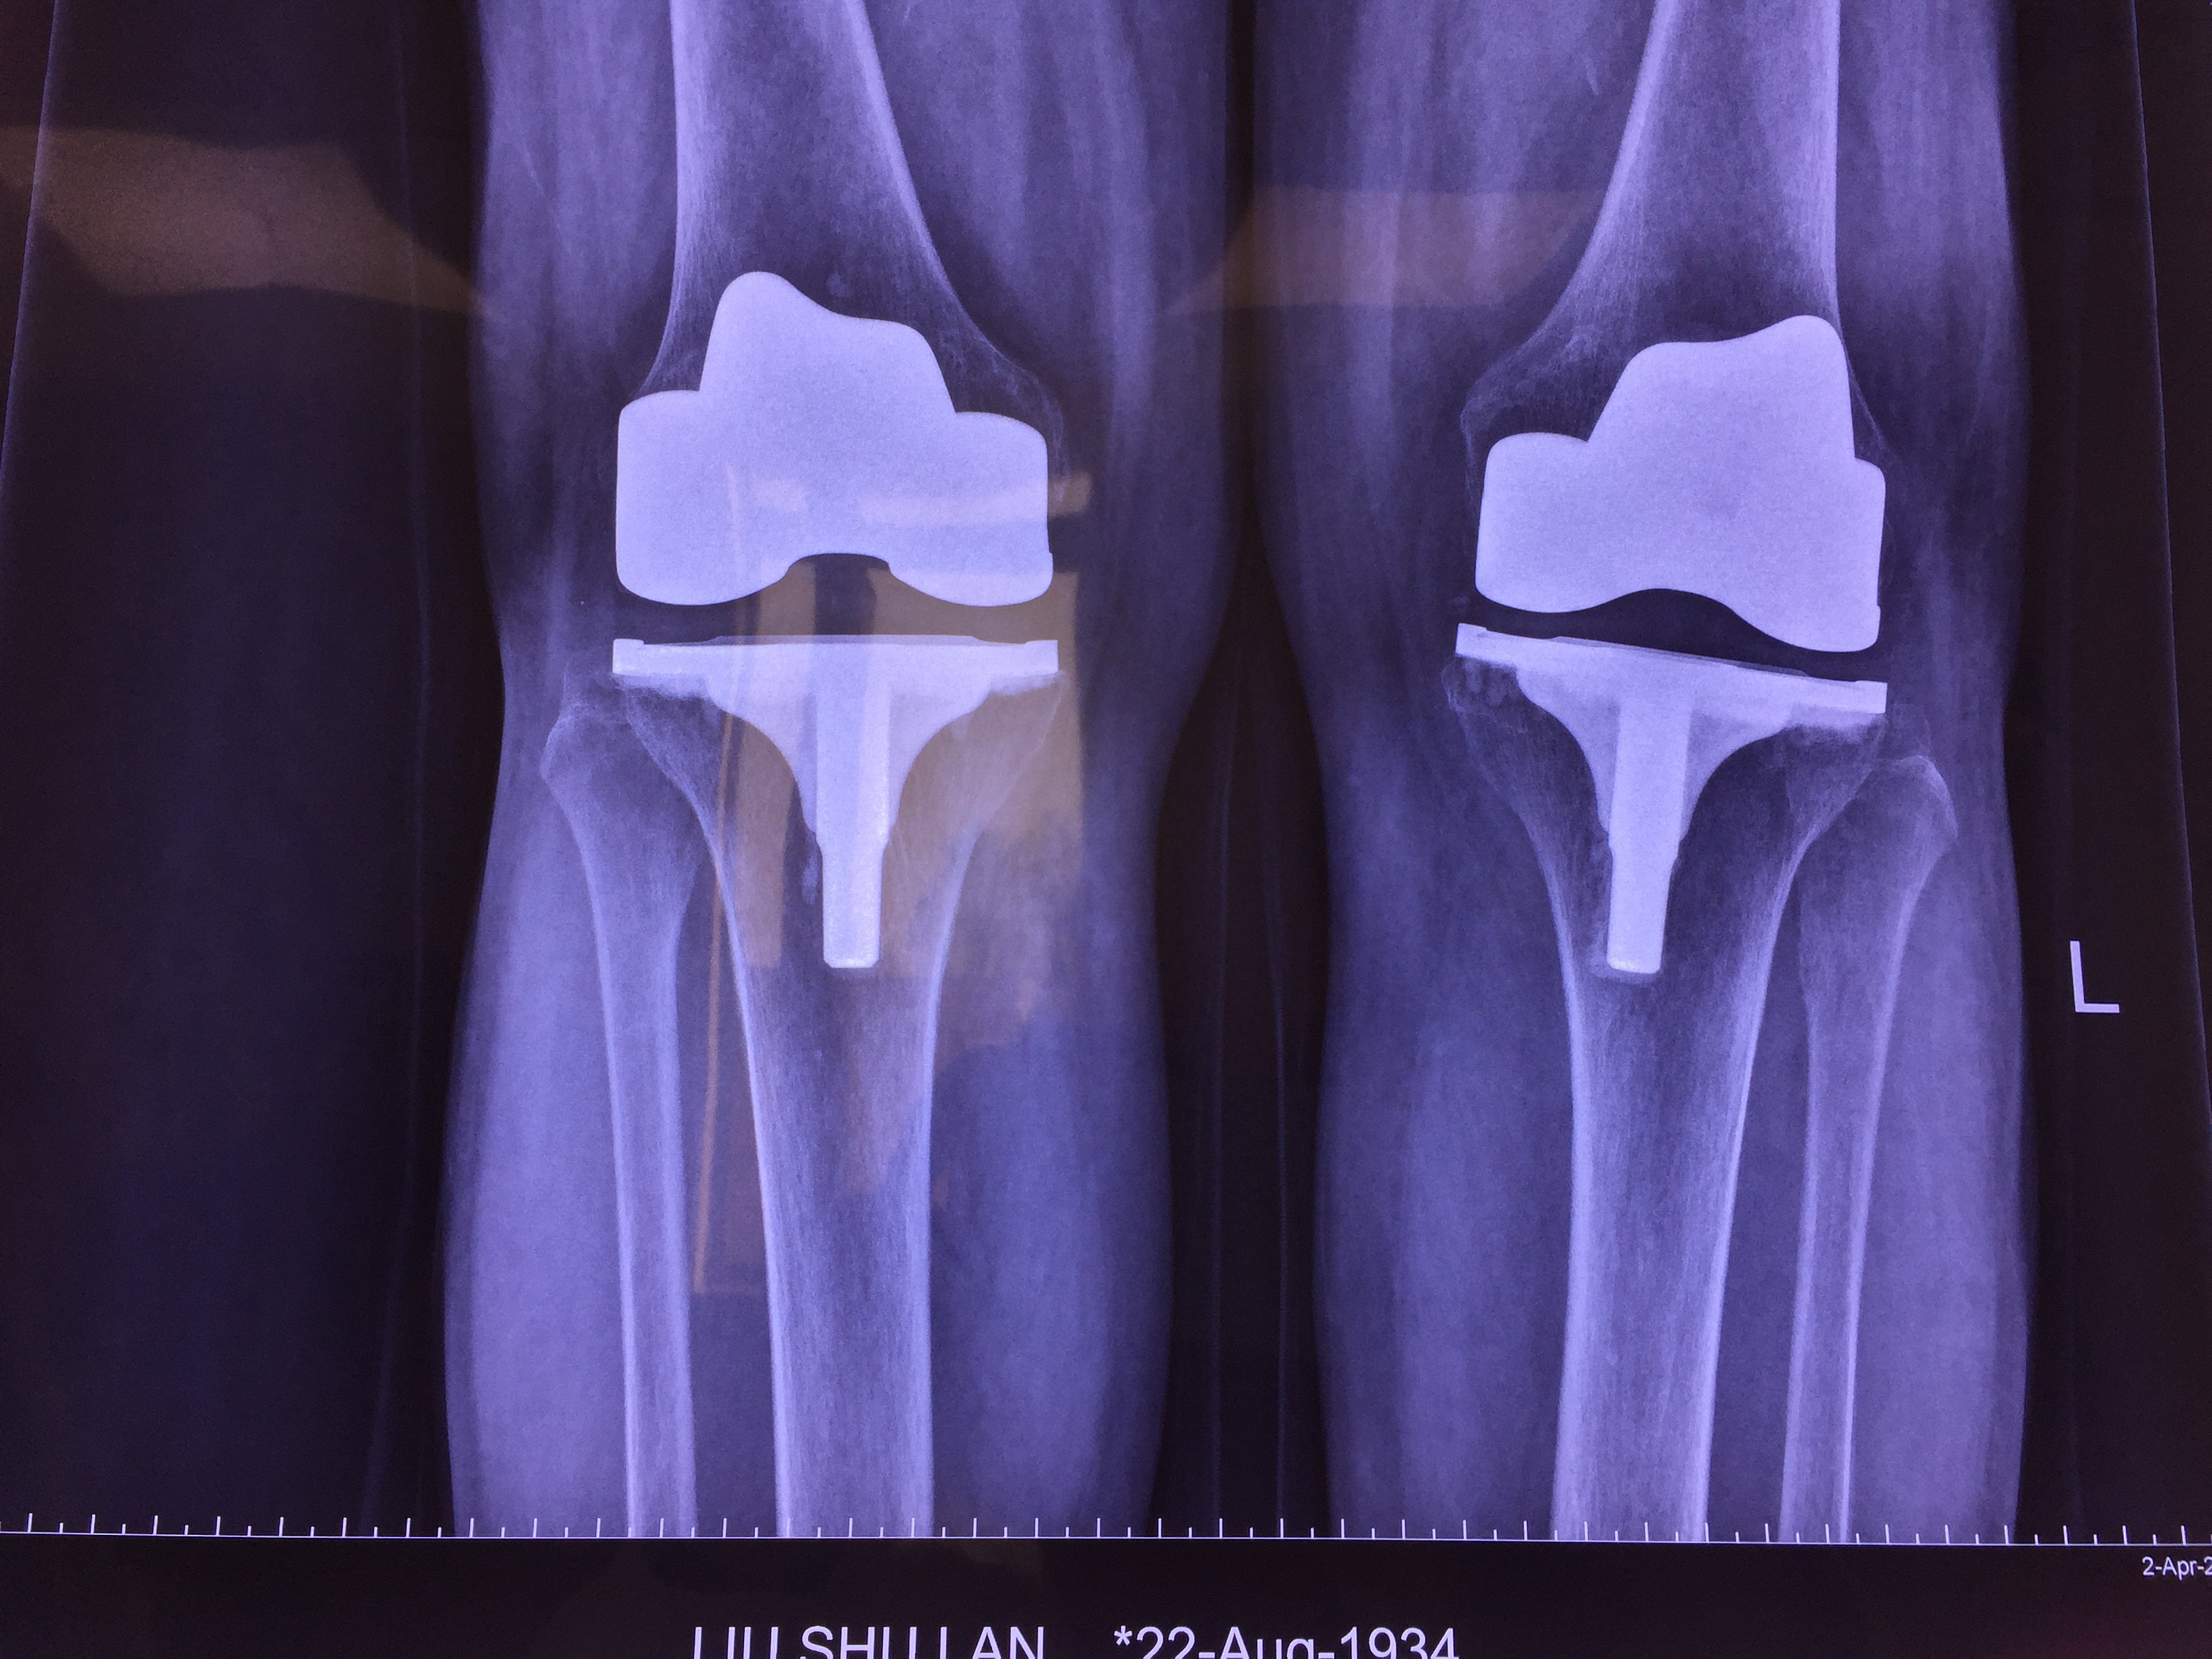

2003年行双膝关节置换 15年后假体固定良好本文是李锋版权所有,未经